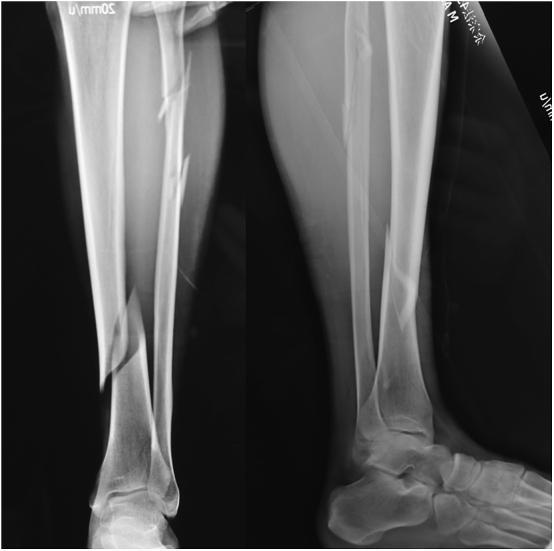

In this non-control prospective study, 28 patients with distal tibial fractures were included and underwent one-stage external fixation by using locking plate. There were 21 males and 7 females, with a mean age of 43 years (19-63). According to AO/OTA fracture classification, there were 9 cases of Type A1, 9 of Type A2, 10 of Type A3 fractures. There were 21 close and 7 open fractures. The locking plate was placed on the anteromedial aspect of the tibia with 4-5 bicortical screws inserted in both distal met- aphysis and diaphysis. The radiographic and clinic results were evaluated.

All patients were followed up for the average of 16 months (ranging from 12 to 21 months). The average surgery duration was 38 (25-60) minutes. The mean time to fracture healing were 14.6 ± 2.67, 17.5 ± 3.66, and 18.4 ± 3.37 (p < 0.05) weeks in type A1, A2, and A3 fractures respectively. By the end of the follow-ups, the mean AOFAS score were 96.11 ± 2.32, 92.67 ± 1.80 and 92.00 ± 2.06 (p > 0.05) in type A1, A2, and A3 fractures respectively. None of nonunion, deep infection, or breakage of screw or plate were observed.

Distal tibial fracture was the ideal indication for external fixation using locking plate. The external plating is characterized by ease of performance, less invasive, fewer soft tissue impingement, improved cosmesis, and convenient for removal.